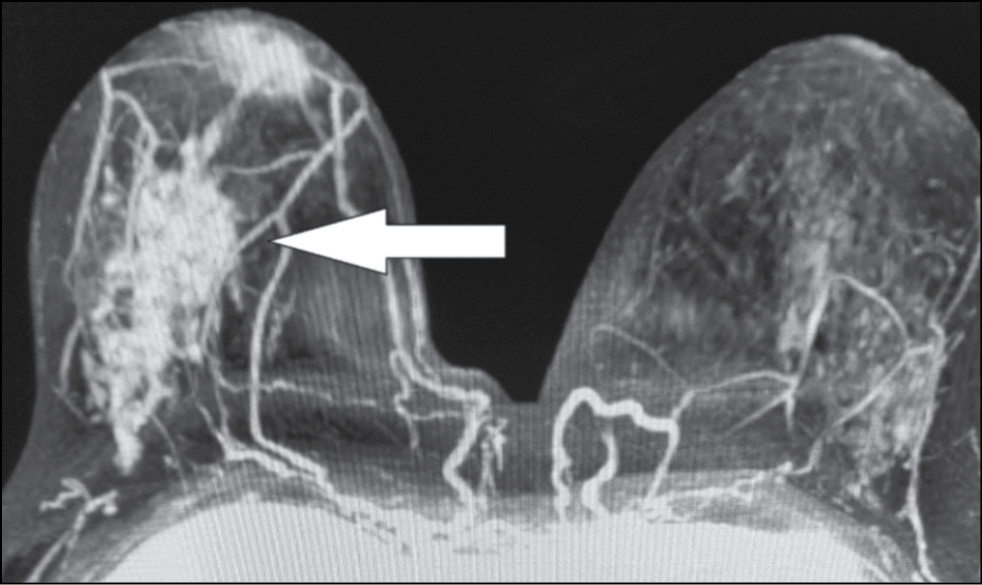

A 59-year-old patient complained of erosive changes in the nipple (Fig. 1). Physical examination revealed erythema, erosion, and nipple retraction. Doppler ultrasonography with color flow mapping revealed increased blood flow in the nipple projection (Fig. 2). Mammography findings were normal. To assess the extent of disease spread, breast MRI with contrast enhancement was performed. The early postcontrast series (Fig. 3) and maximum intensity projection (MIP) images (Fig. 4) showed a segmental contrast retroareolar area from the nipple level to posterior breast sections. Ultrasound-guided core biopsy followed by immunohistochemical analysis revealed Paget’s disease of the nipple with high-grade intraductal carcinoma in situ. Receptors for estrogen (G3 ER) and progesterone (PR) were negative. Oncogenic protein Ki-67 was 45%.

Figure 3. Magnetic resonance imaging of Paget’s disease (early enhancement phase): the retroareolar area of segmental enhancement from the nipple level to the posterior breast (arrow).

Figure 4. Magnetic resonance imaging of Paget’s disease (maximum intensity projection): the retroareolar area of segmental enhancement from the nipple level to the posterior breast (arrow).